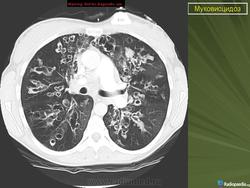

При тщательном обследовании обнаруживается учащенное дыхание, увеличение переднезаднего размера грудной клетки и слабо выраженное, но стойкое втяжение нижних межреберных мышц. Аускультативные патологические признаки могут вообще не выявляться или присутствовать в виде сухих и влажных мелко- и крупнопузырчатых хрипов. На рентгенограмме органов грудной полости выявляют уплотнение стенок бронхов, а также различной степени уплотнение или повышенную воздушность легочной ткани. Могут развиваться ателектазы в сегментах и долях легких, причем поражение правой верхней доли относится к диагностически значимым признакам муковисцидоза.

• ухудшение физикальной и рентгенологической картины в легких;

- Рентгенография органов грудной клетки в прямой и правой боковой проекциях.

• новые рентгенологические изменения в легких (инфильтраты, ателектазы, сливающиеся, гомогенные затемнения или параллельные линейные тени);